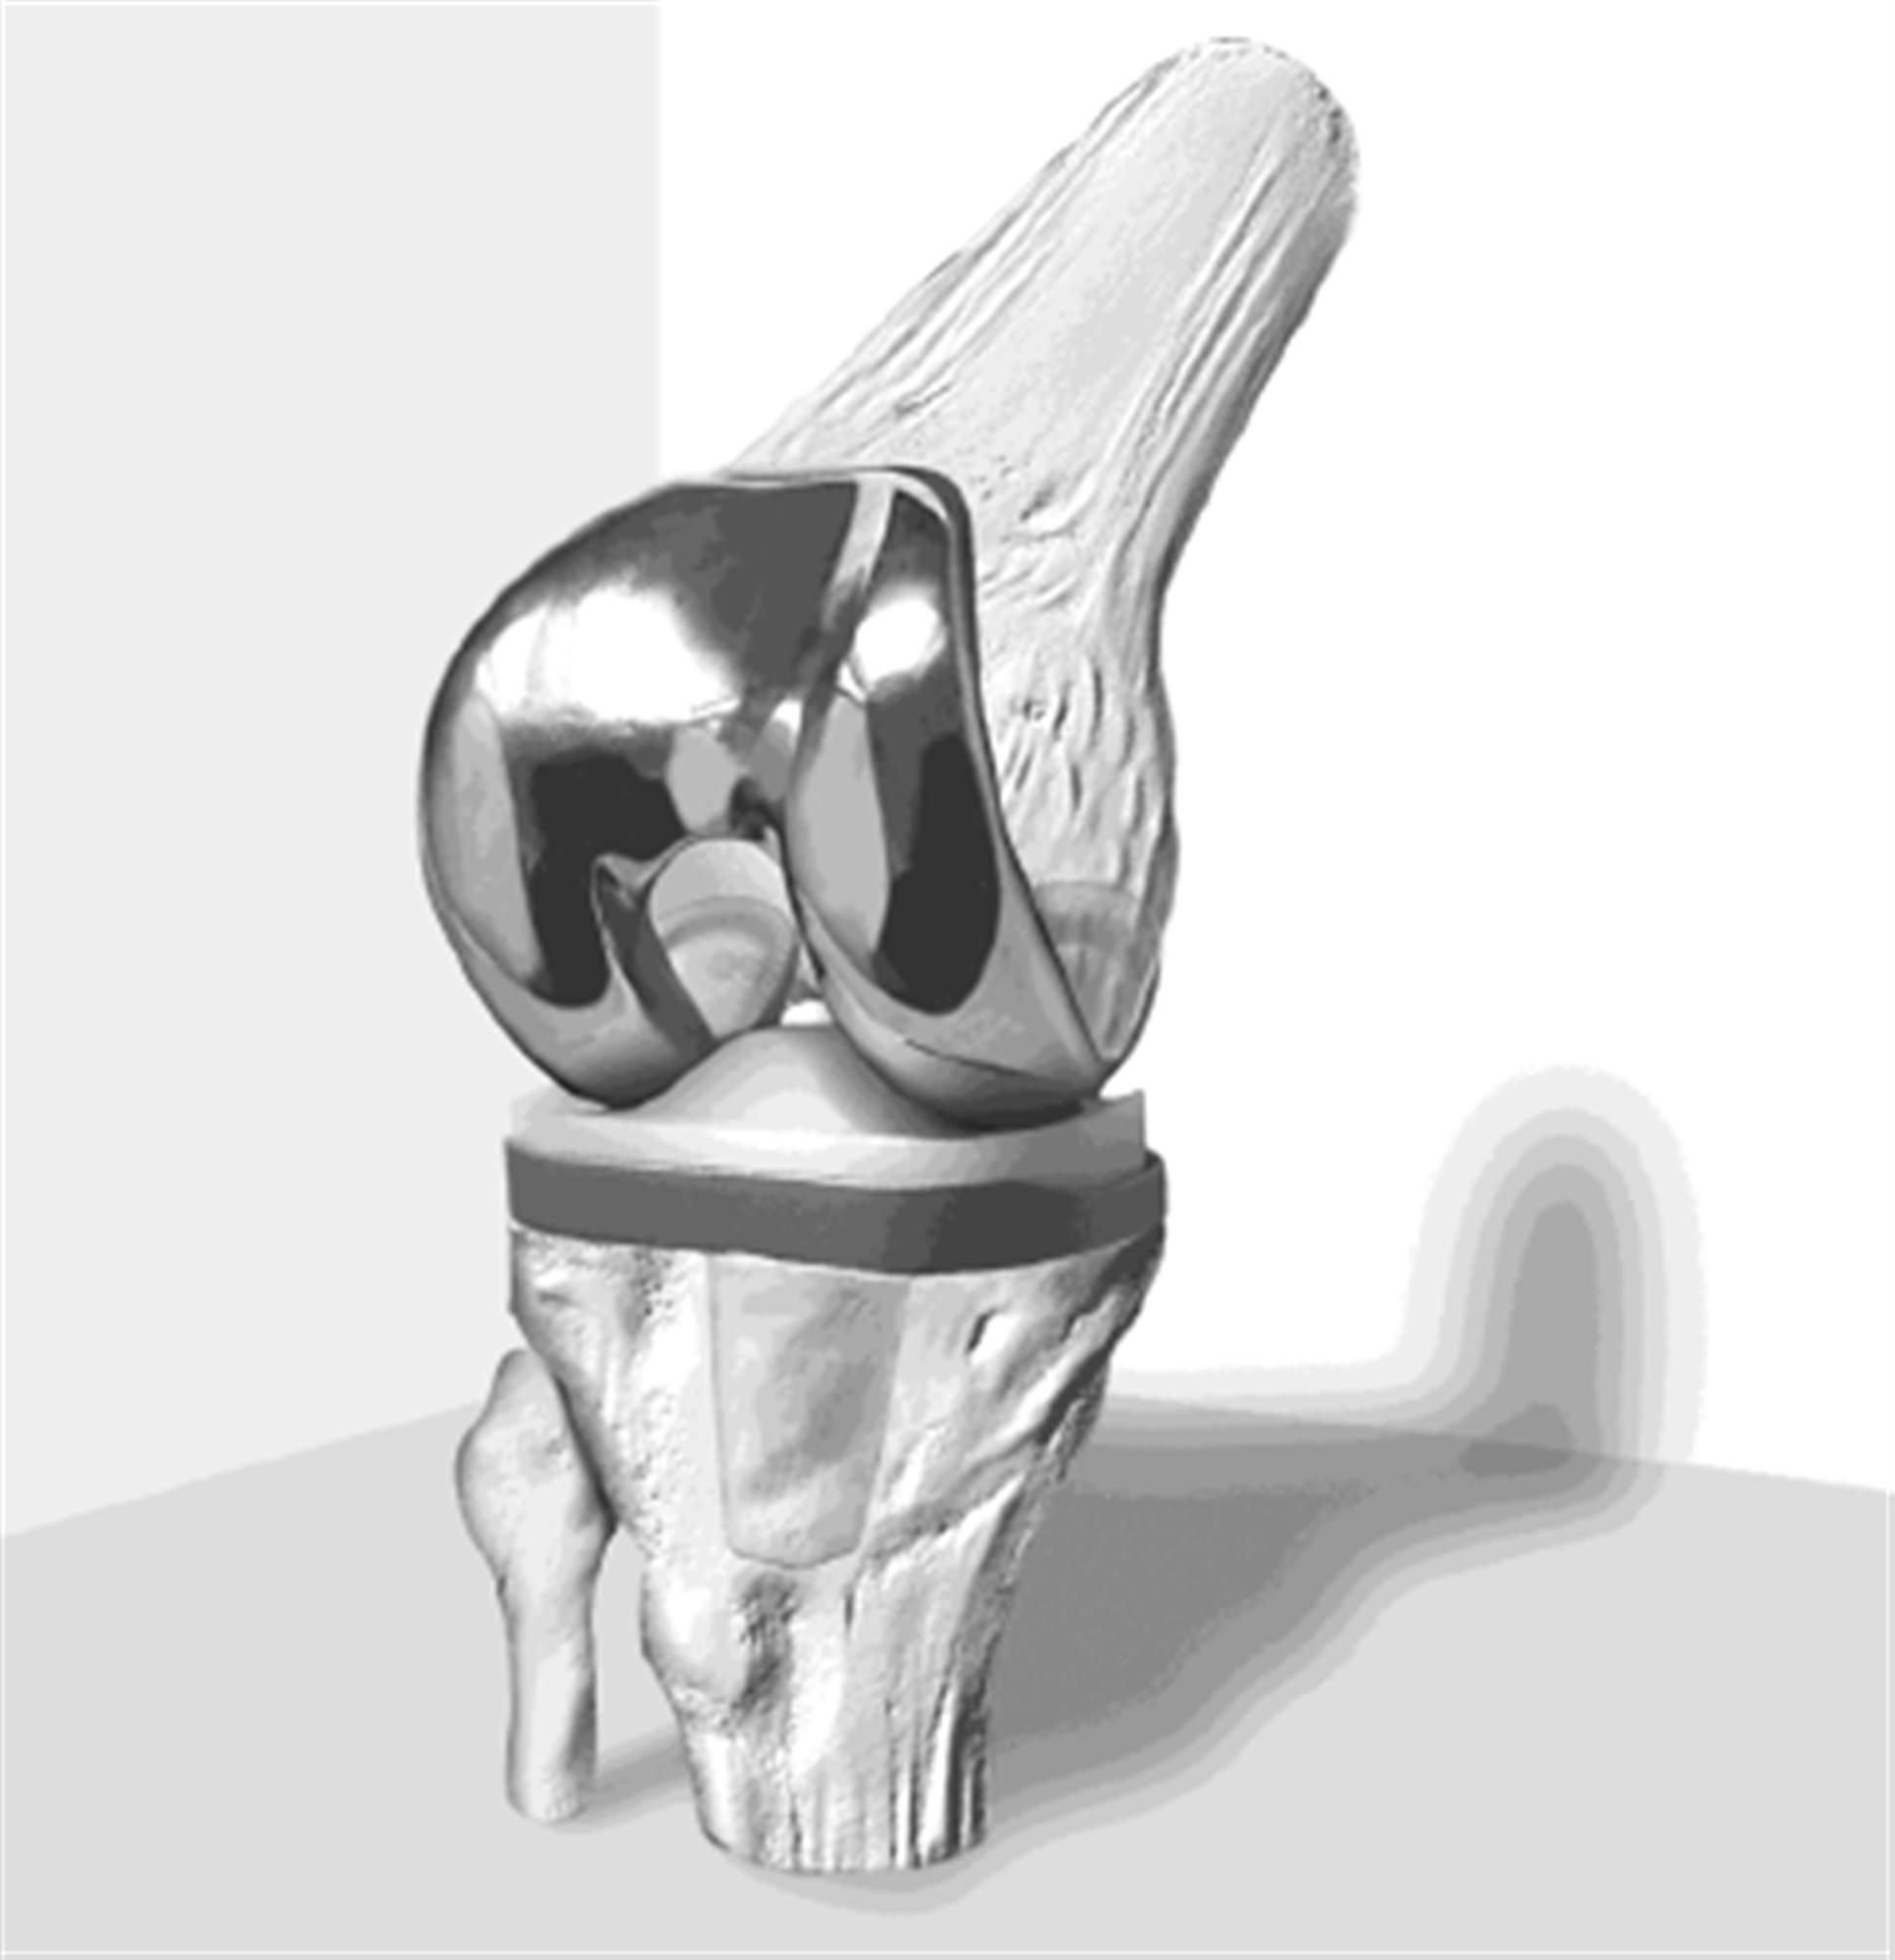

Примеры протезов коленных суставов Zimmer